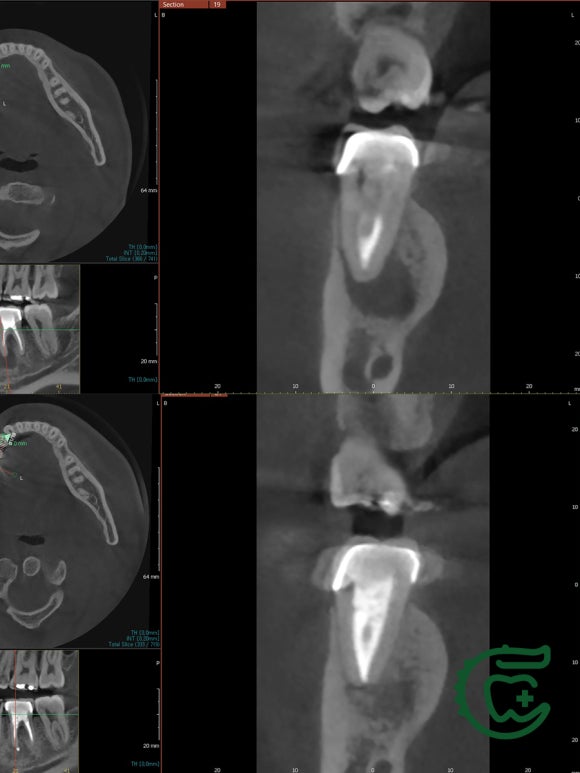

(상) 재신경치료 전 (하) 재신경치료 후

CT로 확인해보면 더욱 만족스럽습니다.

위 사진이 치료 전,

아래 사진이 치료 후 3개월 차에 촬영한

치아의 단면입니다.

거의 완치수준이라고 봐도 될것입니다.

바쁜 수험 생활에도 불구하고

치료에 전념해주신 ㄱㅅㅇ님께

감사의 말씀을 전합니다.